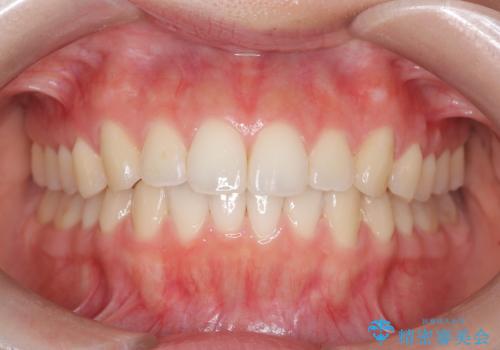

【ワイヤー矯正】八重歯 歯のでこぼこを治したい!